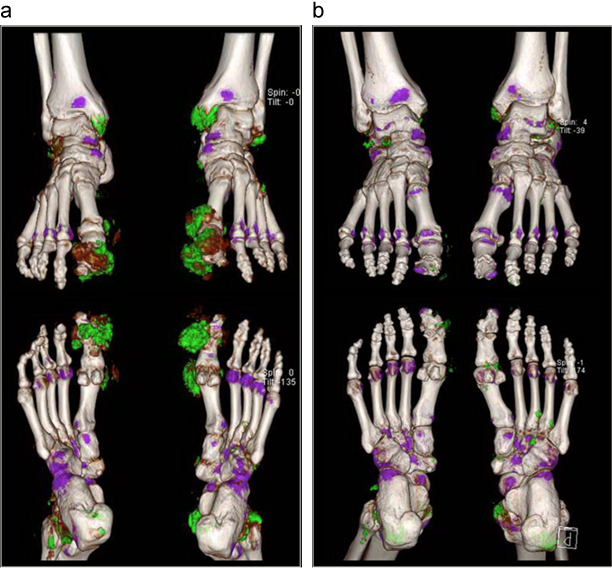

痛風のDECT像

拇趾基関節や足関節にMSU結晶がグリーンの沈着物として示される。8カ月の尿酸降下療法でMSU沈着の減少がみられる(b)。

出典

imgimg

1: Identification of vanishing tophi by three-dimensional dual-energy computed tomography in a patient with chronic tophaceous gout.

著者: Jung SM, Ju JH.

雑誌名: Clin Case Rep. 2016 Jan;4(1):97-8. doi: 10.1002/ccr3.440. Epub 2015 Nov 12.

Abstract/Text: Large gout tophi are difficult to treat and sometimes needs operation for its elimination. Dual-energy computed tomography (DECT) is now being used for detection of tophi in patients with gouty arthritis. After intensive treatment, we could observe vanishing tophi with DECT.

Clin Case Rep. 2016 Jan;4(1):97-8. doi: 10.1002/ccr3.440. Epub 2015 No...